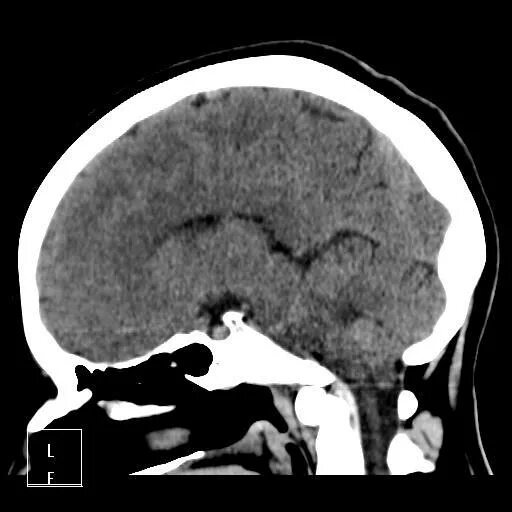

Миндалины на кт